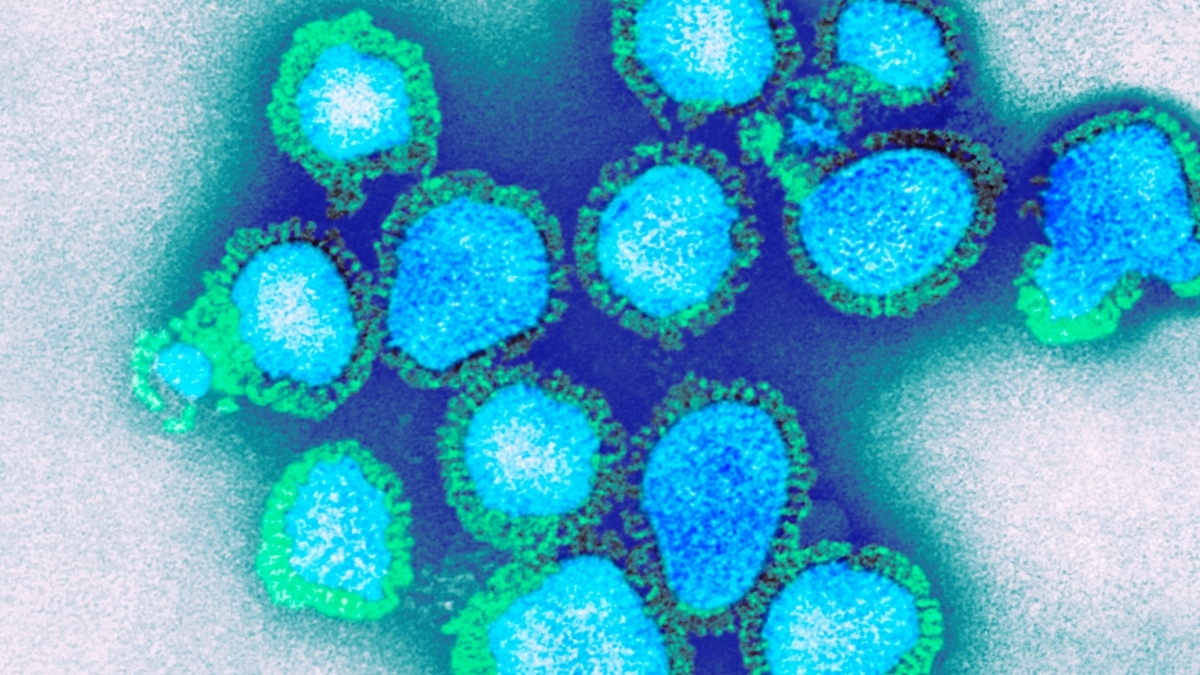

The brain has its own waste disposal system – known as the glymphatic system – that’s thought to be more active when we sleep.

But disrupted sleep might hinder this waste disposal system and slow the clearance of waste products or toxins from the brain. And researchers are proposing a build-up of these toxins due to lost sleep could increase someone’s risk of dementia.

There is still some debate about how this glymphatic system works in humans, with most research so far in mice.

But it raises the possibility that better sleep might boost clearance of these toxins from the human brain and so reduce the risk of dementia.

Here’s what we know so far about this emerging area of research.

All cells in the body create waste. Outside the brain, the lymphatic system carries this waste from the spaces between cells to the blood via a network of lymphatic vessels.

But the brain has no lymphatic vessels. And until about 12 years ago, how the brain clears its waste was a mystery. That’s when scientists discovered the “glymphatic system” and described how it “flushes out” brain toxins.

Let’s start with cerebrospinal fluid, the fluid that surrounds the brain and spinal cord. This fluid flows in the areas surrounding the brain’s blood vessels. It then enters the spaces between the brain cells, collecting waste, then carries it out of the brain via large draining veins.

Scientists then showed in mice that this glymphatic system was most active – with increased flushing of waste products – during sleep.

One such waste product is amyloid beta (Aβ) protein. Aβ that accumulates in the brain can form clumps called plaques. These, along with tangles of tau protein found in neurons (brain cells), are a hallmark of Alzheimer’s disease, the most common type of dementia.

In humans and mice, studies have shown that levels of Aβ detected in the cerebrospinal fluid increase when awake and then rapidly fall during sleep.

But more recently, another study (in mice) showed pretty much the opposite – suggesting the glymphatic system is more active in the daytime. Researchers are debating what might explain the findings.

So we still have some way to go before we can say exactly how the glymphatic system works – in mice or humans – to clear the brain of toxins that might otherwise increase the risk of dementia.

We know sleeping well is good for us, particularly our brain health. We are all aware of the short-term effects of sleep deprivation on our brain’s ability to function, and we know sleep helps improve memory.

In one experiment, a single night of complete sleep deprivation in healthy adults increased the amount of Aβ in the hippocampus, an area of the brain implicated in Alzheimer’s disease. This suggests sleep can influence the clearance of Aβ from the human brain, supporting the idea that the human glymphatic system is more active while we sleep.

This also raises the question of whether good sleep might lead to better clearance of toxins such as Aβ from the brain, and so be a potential target to prevent dementia.

What is less clear is what long-term disrupted sleep, for instance if someone has a sleep disorder, means for the body’s ability to clear Aβ from the brain.

Sleep apnoea is a common sleep disorder when someone’s breathing stops multiple times as they sleep. This can lead to chronic (long-term) sleep deprivation, and reduced oxygen in the blood. Both may be implicated in the accumulation of toxins in the brain.

Sleep apnoea has also been linked with an increased risk of dementia. And we now know that after people are treated for sleep apnoea more Aβ is cleared from the brain.

Insomnia is when someone has difficulty falling asleep and/or staying asleep. When this happens in the long term, there’s also an increased risk of dementia. However, we don’t know the effect of treating insomnia on toxins associated with dementia.

So again, it’s still too early to say for sure that treating a sleep disorder reduces your risk of dementia because of reduced levels of toxins in the brain.

Collectively, these studies suggest enough good quality sleep is important for a healthy brain, and in particular for clearing toxins associated with dementia from the brain.

But we still don’t know if treating a sleep disorder or improving sleep more broadly affects the brain’s ability to remove toxins, and whether this reduces the risk of dementia. It’s an area researchers, including us, are actively working on.

For instance, we’re investigating the concentration of Aβ and tau measured in blood across the 24-hour sleep-wake cycle in people with sleep apnoea, on and off treatment, to better understand how sleep apnoea affects brain cleaning.

Researchers are also looking into the potential for treating insomnia with a class of drugs known as orexin receptor antagonists to see if this affects the clearance of Aβ from the brain.

This is an emerging field and we don’t yet have all the answers about the link between disrupted sleep and dementia, or whether better sleep can boost the glymphatic system and so prevent cognitive decline.

So if you are concerned about your sleep or cognition, please see your doctor.![]()